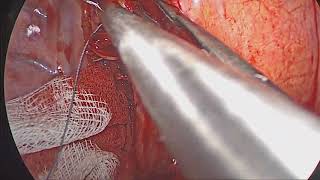

Concern for dehiscence of bronchial suture post pneumonectomy video

Concern for dehiscence of bronchial suture post pneumonectomy

Concern for dehiscence of bronchial suture post pneumonectomy Delayed Bronchial Dehiscence - BPF Post Pneumonectomy - Bronchoscopy Closure

Concern for dehiscence of bronchial suture post pneumonectomy

Concern for dehiscence of bronchial suture post pneumonectomy Delayed Bronchial Dehiscence - BPF Post Pneumonectomy - Bronchoscopy Closure